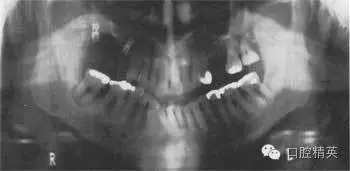

圖38.2 患者牙齒的全口牙位曲面體層X線片

牙齒全口牙位曲面體層X線片如圖38.2所示,你看到了什么?

答:全口牙位曲面體層X線片不是很清晰。患者頭位沒擺正,使圖像產(chǎn)生很大扭曲。下頜骨下緣呈彎曲圖像,且下前牙被縮短了。因?yàn)轶w位不正,脊柱陰影也被增強(qiáng)了。因?yàn)橛跋裰丿B,中線處的牙齒沒在中點(diǎn)。頭偏向一邊,一側(cè)影像被放大。這在后牙牙冠上很容易看出來,因?yàn)橛覀?cè)比左側(cè)的牙冠大?;颊叩男g(shù)后片如圖38.3,它顯示了正常片子應(yīng)顯示的樣子。

X線片顯示,了右下及左下第二磨牙周圍廣泛的骨質(zhì)破壞。左下第二磨牙有骨喪失并有根分叉處齲壞。下頜兩個(gè)第一磨牙有明顯的根分叉病變,但卻不松動(dòng)。